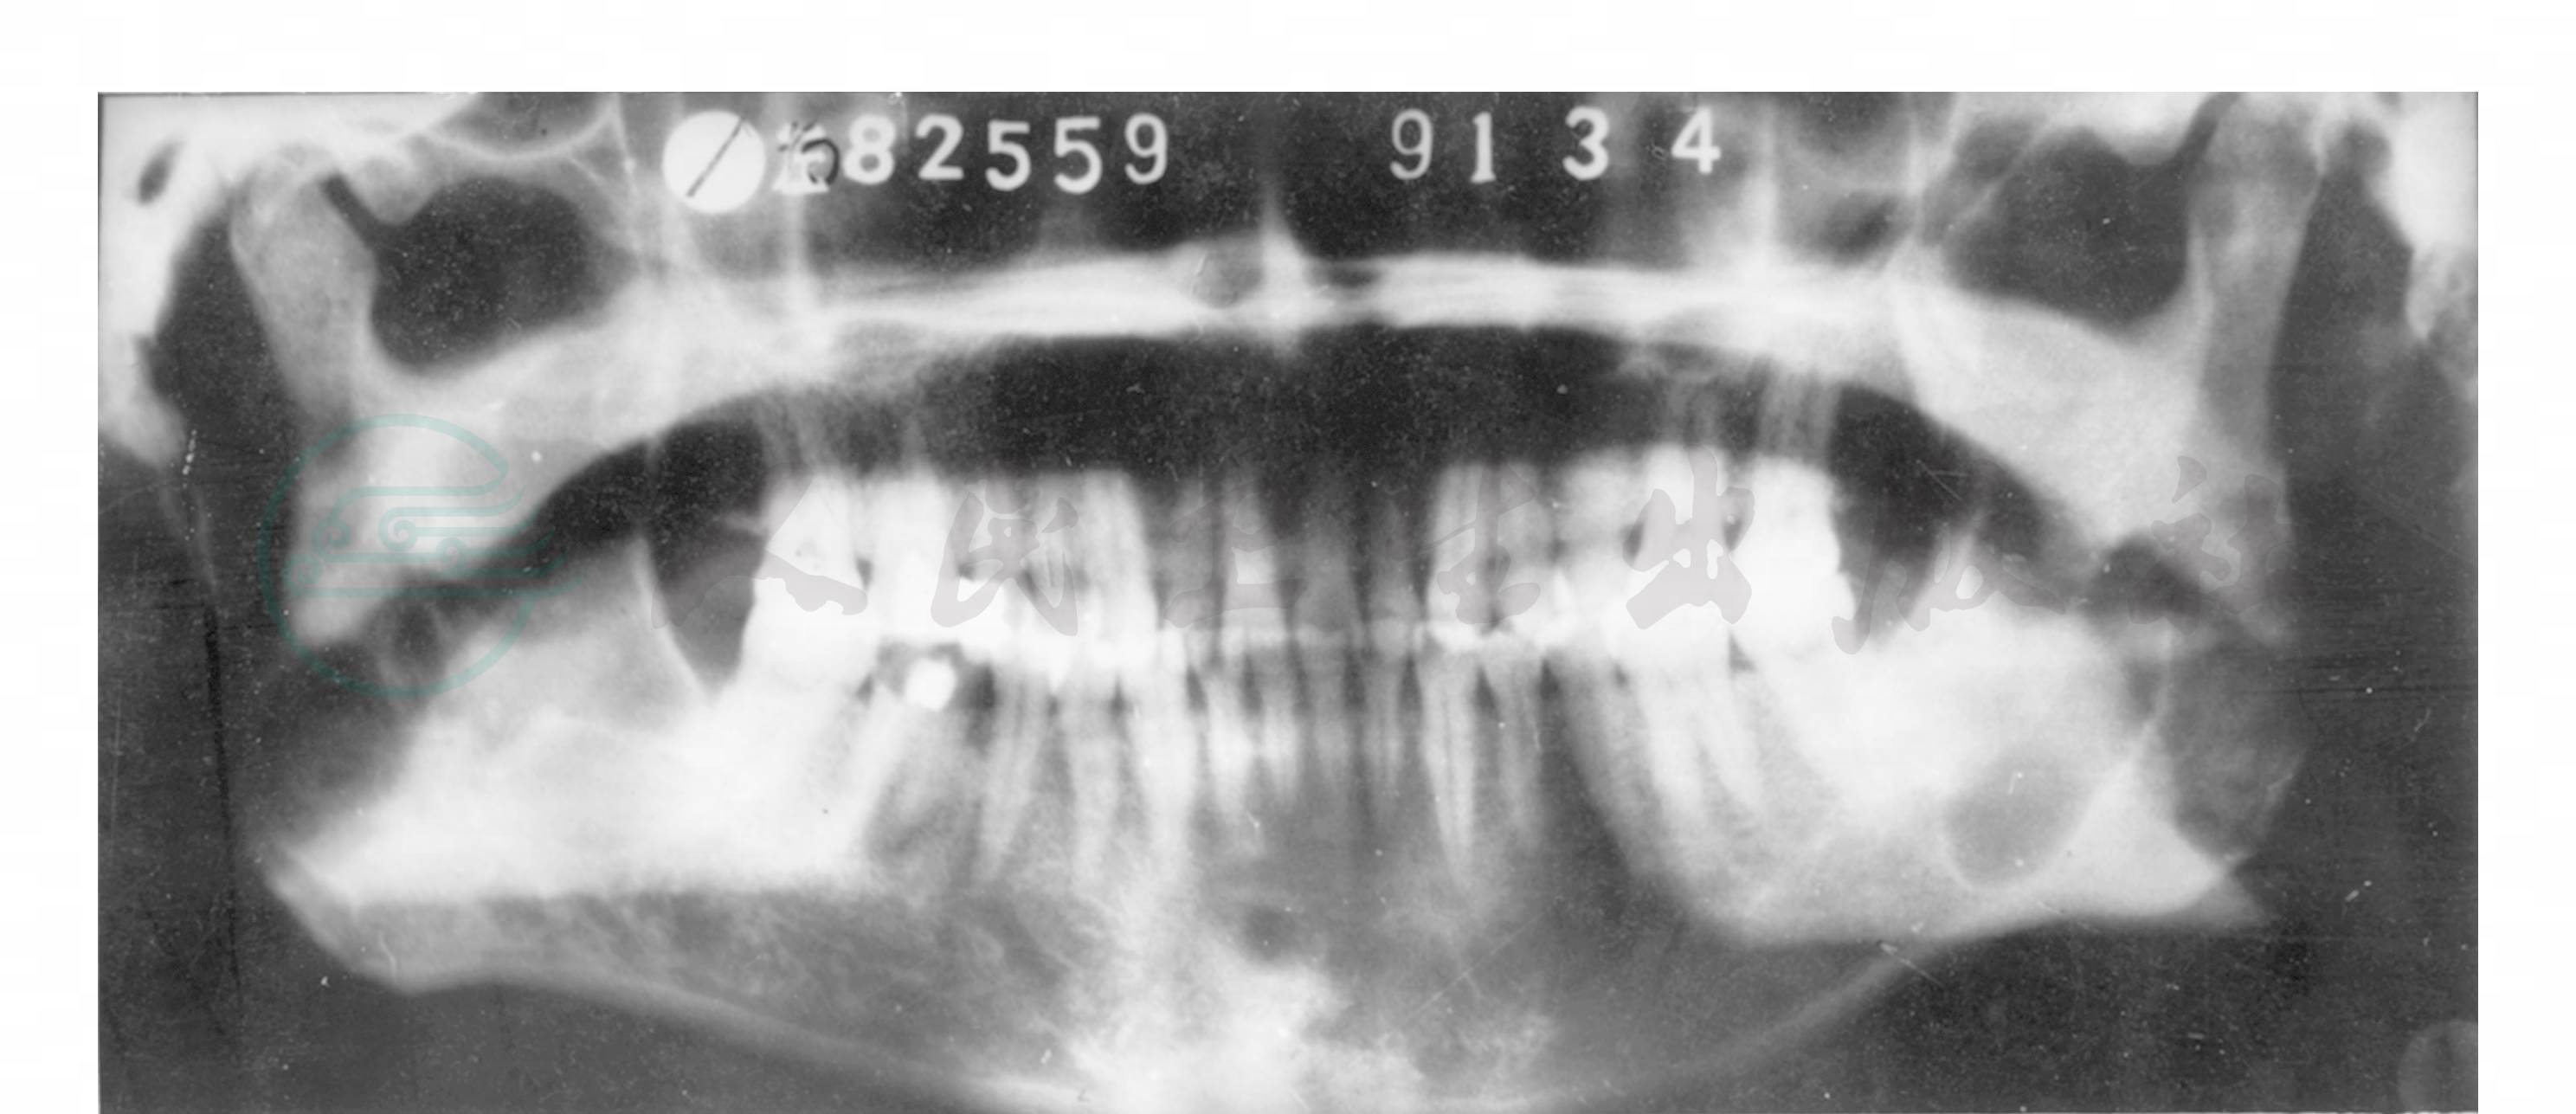

牙源性角化囊肿可以是单囊型透影区,也可呈现为多囊性。上下颌多发并非少见,因此囊肿术后诊断为角化囊肿时,全口牙位曲面体层X线片检查是必要的(图3)。多发性角化囊肿囊形透影区大小相差不大,常沿颌骨长轴发展而较少颌骨膨胀。有时透影区密度极低,表明囊肿穿破骨皮质而侵入软组织。牙齿移位不常见,偶见根尖吸收。有时囊形阴影区内可见有牙齿,但手术证实牙齿并非在囊腔内,而是在其生长发育过程中受压移位阻生所致。文献报道,正角化型角化囊肿80%为单囊型密度降低区,非常类似含牙囊肿的X线表现。

图3 牙源性角化囊肿 (多发)